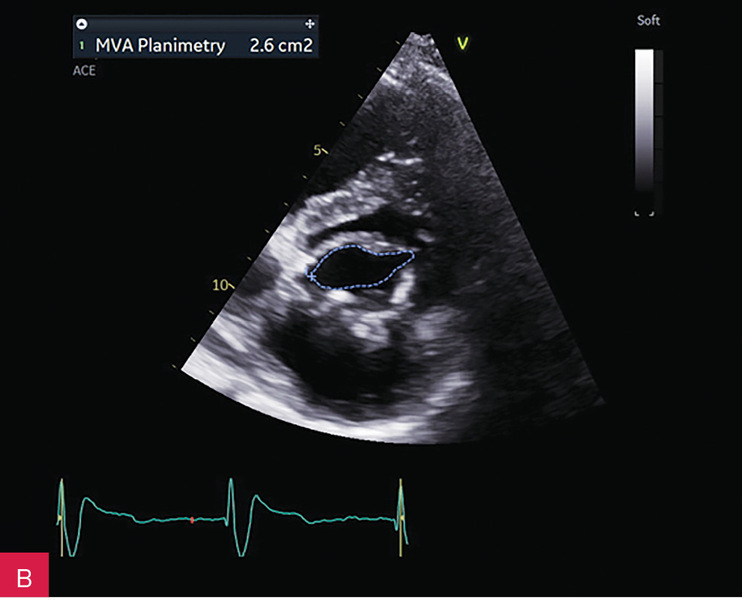

W badaniu echokardiograficznym przezklatkowym (TTE – transthoracic echocardiography) uwidoczniono guzowatą zmianę o wymiarach 37 × 28 × 25 mm u podstawy tylnego płatka zastawki mitralnej i w obrębie ściany dolno-bocznej lewej komory, o nierównej powierzchni od strony komory, nieznacznej ruchomości zgodnej z ruchem serca i niejednorodnej echostrukturze ze zwapnieniami (ryc. 2-5). Powodowała ona niewielkie ograniczenie ruchomości płatków zastawki mitralnej z utrudnieniem napełniania komory i parametrami małej stenozy (ryc. 6). Stwierdzono ponadto małą niedomykalność mitralną (ryc. 6), dużą niedomykalność trójdzielną, znacznie powiększone obydwa przedsionki oraz w niewielkim stopniu prawą komorę w zakresie drogi odpływu, a także niewielki przerost ścian lewej komory. W badaniu nie stwierdzono wyraźnych odcinkowych zaburzeń kurczliwości lewej komory. Globalna funkcja skurczowa lewej i prawej komory była zachowana w dolnych granicach normy: frakcja wyrzutowa lewej komory (LVEF – left ventricular ejection fraction) 50%, skurczowe przemieszczenie płaszczyzny pierścienia trójdzielnego (TAPSE – tricuspid annular plane systolic excursion) 18 mm. Stwierdzono cechy dysfunkcji rozkurczowej lewej komory z cechami wysokiego ciśnienia napełniania. Zarejestrowano również małą ilość płynu w osierdziu (do 6 mm za ścianą boczną lewej komory).

Rycina 9A-C. Kontrolne badanie echokardiograficzne przezklatkowe (TTE) po 5 miesiącach od rozpoznania uwidoczniło porównywalne wymiary zmiany guzowatej jak w badaniu wyjściowym (A), brak progresji zwężenia zastawki mitralnej (B), charakterystyczny obraz uwapnionej otoczki z bezechowym rdzeniem wewnętrznym (C)